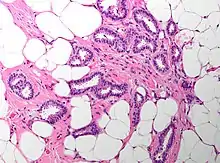

| Cribriform carcinoma of the breast showing a cribriform area | |

Invasive cribriform carcinoma of the breast (ICCB), also termed invasive cribriform carcinoma, is a rare type of breast cancer that accounts for 0.3% to 0.6% of all carcinomas (i.e. cancers that develop from epithelial cells) in the breast.[1] It originates in a lactiferous duct as opposed to the lobules that form the alveoli in the breasts' mammary glands (lobules make the milk which the ducts channel to the breast's nipple). ICCB was first described by Dixon and colleagues in 1983 as a tumor that on microscopic histopathological inspection had a cribriform pattern,[2] i.e. a tissue pattern consisting of numerous "Swiss cheese"-like open spaces and/or sieve-like small holes (see adjacent Figure).[3] The latest edition (2019) of the World Health Organization (2019) termed these lesions invasive cribriform carcinomas indicating that by definition they must have a component that invades out of their ducts of origin into adjacent tissues. In situ ductal cancers (i.e. cancers localized entirely within their tissues of origin) that have a cribriform histopathology are regarded as belonging to the group of ductal carcinoma in situ tumors.[4]

The microscopic histopathology of ICCB tumors stained with hematoxylin and eosin shows cribriform areas covering more than 50% of the tumor with the remaining tumor areas showing tubular and/or other histopathological patterns. The cribriform areas consist of small-sized cells with amphophilic (i.e. taking up both the hematoxylin and eosin stains) cytoplasm, indistinct cell boundaries, and small-to-medium sized nuclei that are surrounded by a sharp nuclear membrane and contain finely stippled chromatin (i.e. DNA coated with protein).[17] Numerous open spaces and/or sieve-like small holes lie between these cells (see above photomicrograph) to give the lesions a Swiss cheese-like appearance. The spaces and holes may contain microcalcifications and/or mucins (i.e. high molecular weight, sugar-linked proteins normally produced and secreted by the mammary gland and found in milk).[3] The cells around these spaces and holes sometimes have "apical snouts", i.e. small protrusions on the side of the cells that faces the spaces and holes.[11] Tubular areas (see adjacent photomicrograph of a tubular carcinoma) consist of well-formed tubules lined with mostly normal appearing tubular cells.[17][20] The other histopathological patterns that may occur in these tumor types include the pattern associated with invasive carcinoma of no special type[4] or in uncommon cases the pattern associated with mucinous carcinoma of the breast.[17] The invasive component of these tumors almost always has the cribriform histopathology pattern.[14] All of the tumor cells in ICCB are typically slow-growing as evidenced by their low mitotic index (i.e. the ratio of the number of dividing cells to the total number of tumor cells) or low levels of cellular Ki-67 protein (an index of cell proliferation).[14]